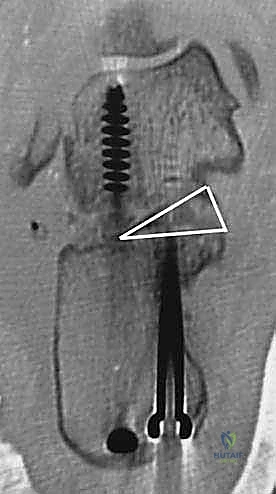

- دمج المفصل تحت الكاحل (Subtalar Arthrodesis):

في الغالبية العظمى من حالات سوء الالتئام، يكون المفصل تحت الكاحل قد تدمر تماماً بسبب الخشونة والاحتكاك. الحل الجذري والنهائي للألم هنا هو "دمج" أو "تثبيت" هذا المفصل. يقوم الدكتور هطيف بتنظيف الغضاريف التالفة بالكامل، ووضع العظام في وضعها التشريحي الصحيح، ثم تثبيتها باستخدام براغي معدنية قوية جداً (Screws) لتلتحم وتصبح عظمة واحدة صلبة خالية من الألم.

- يتم إجراء أشعة سينية للتأكد من بدء التئام العظام والتحام المفصل.